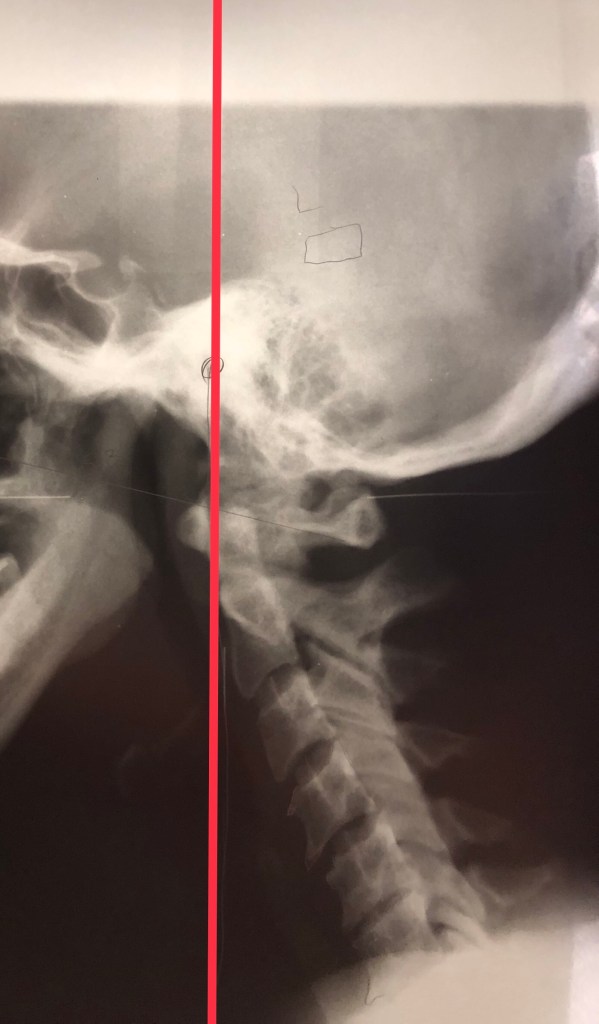

1st full year of medication – I had just started IVO2 and soft braceThese people are my life Irlen Lens SelectionGem/light and cardio synchronization at Hansa (2017) Gem/light and cardio synchronization at Hansa (2019)Neuro feedback (Biologix 2019)ST8 and Split O2Biomat (Biologix 2019)Dr. Martin Hart (Hansa)Amazing Staff at Biologix (formerly Hansa 2019)Cervical misalignmentCervical MisalignmentOzone therapySwelling happensTractionWheelchair is sometimes necessary (not as often anymore)Road trips for treatmentMast Cell Activation can cause lots of rashesAspen CollarProlotherapy (with nitrous)ProlotherapyProlotherapyOuchDr. Kison FrankThe Lovely Elise at Docere Life Center